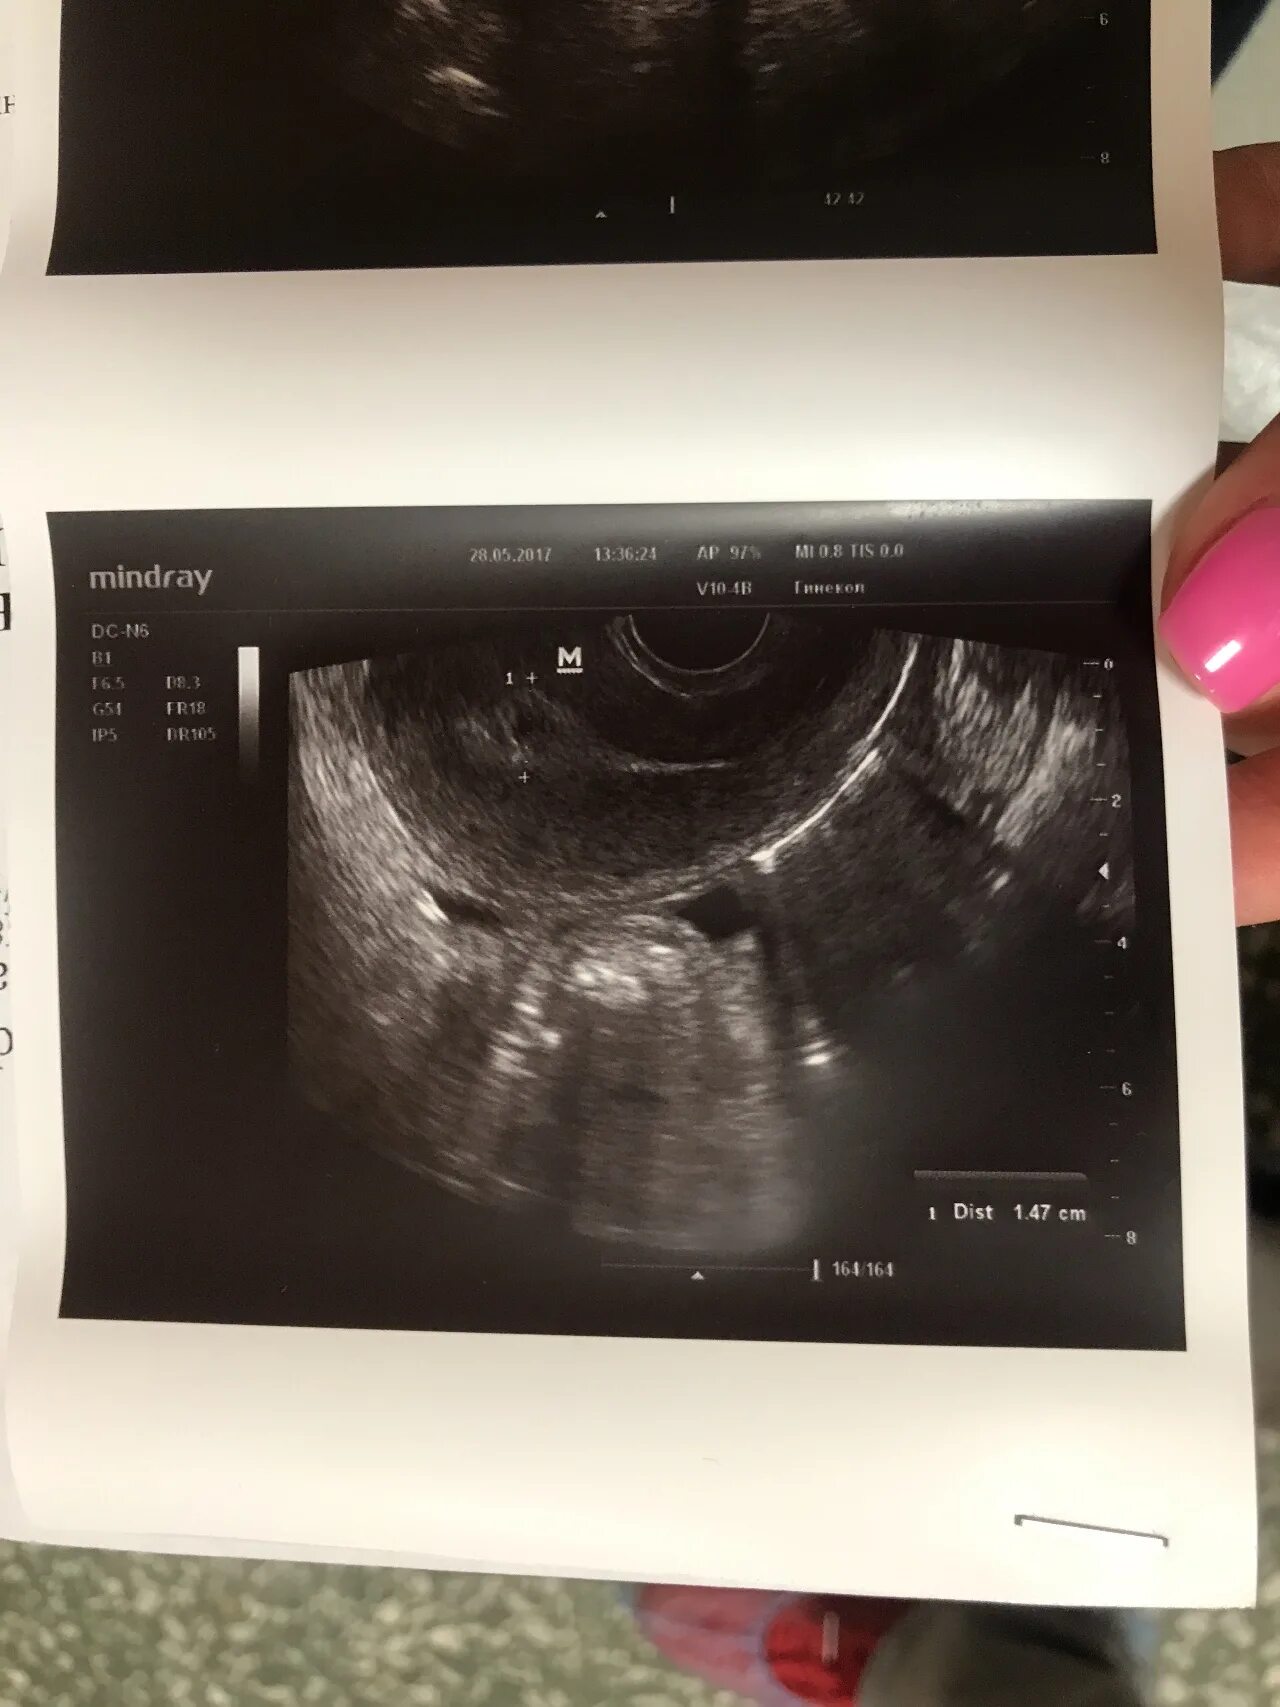

Выделения после вакуумной